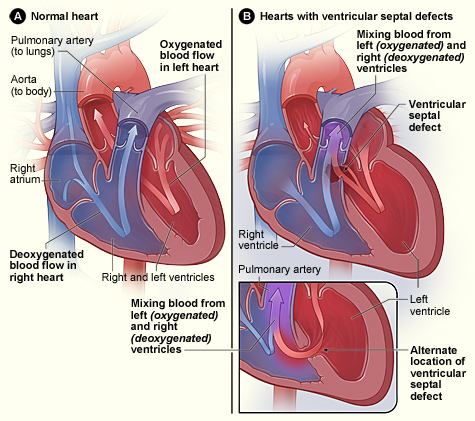

Ventricular Septal Defect (VSD)

A ventricular septal defect is a flaw in the wall that separates the right and left ventricles, or septum.

Ventricular septal defect is the most common congenital cardiac condition.

Ventricular septal defect is inextricably linked to fetal alcohol syndrome.

Ventricular septal defect results in a shunt from left to right.

Age at presentation and defect size both depend on the ventricular septal defect size.

Large ventricular septal defect can cause Eisenmenger syndrome.

Treatment of large ventricular septal defect involves surgery.

Small ventricular septal defects are frequently asymptomatic.

Small flaws might naturally close.